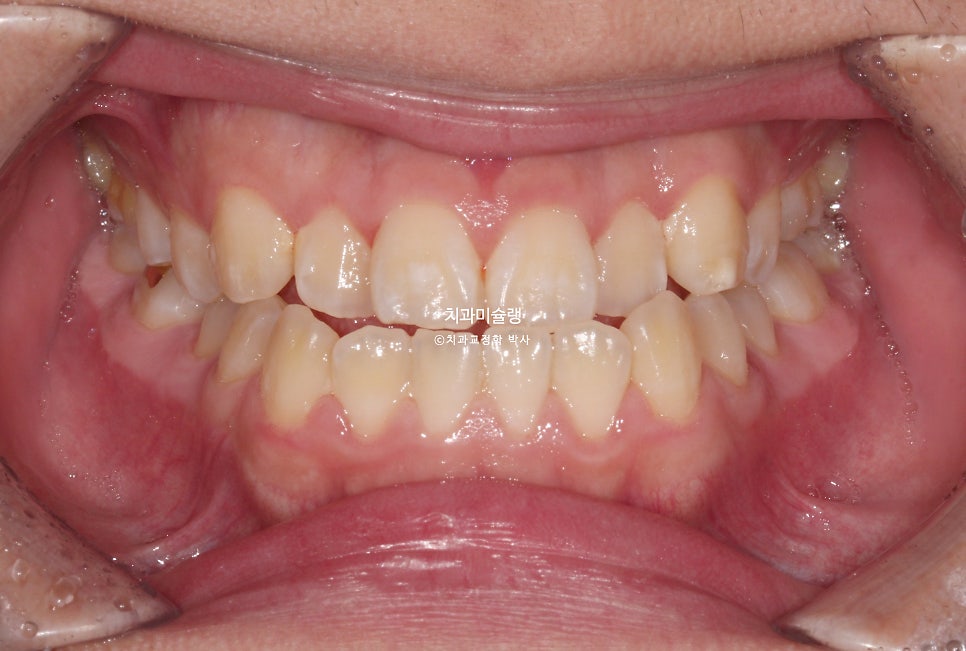

2024년 1월, 교정치료를 위해 내원한 20대 초반 환자분 입니다.

앞니에 약간의 개방교합이 보이고

앞니가 거꾸로 물리는 반대교합입니다.

치아만 거꾸로 물리는에 아닌, 골격성 3급 부정교합으로 양악수술이 필요한 주걱턱 입니다.

어금니도 마찬가지로 3급 교합관계를 보입니다.